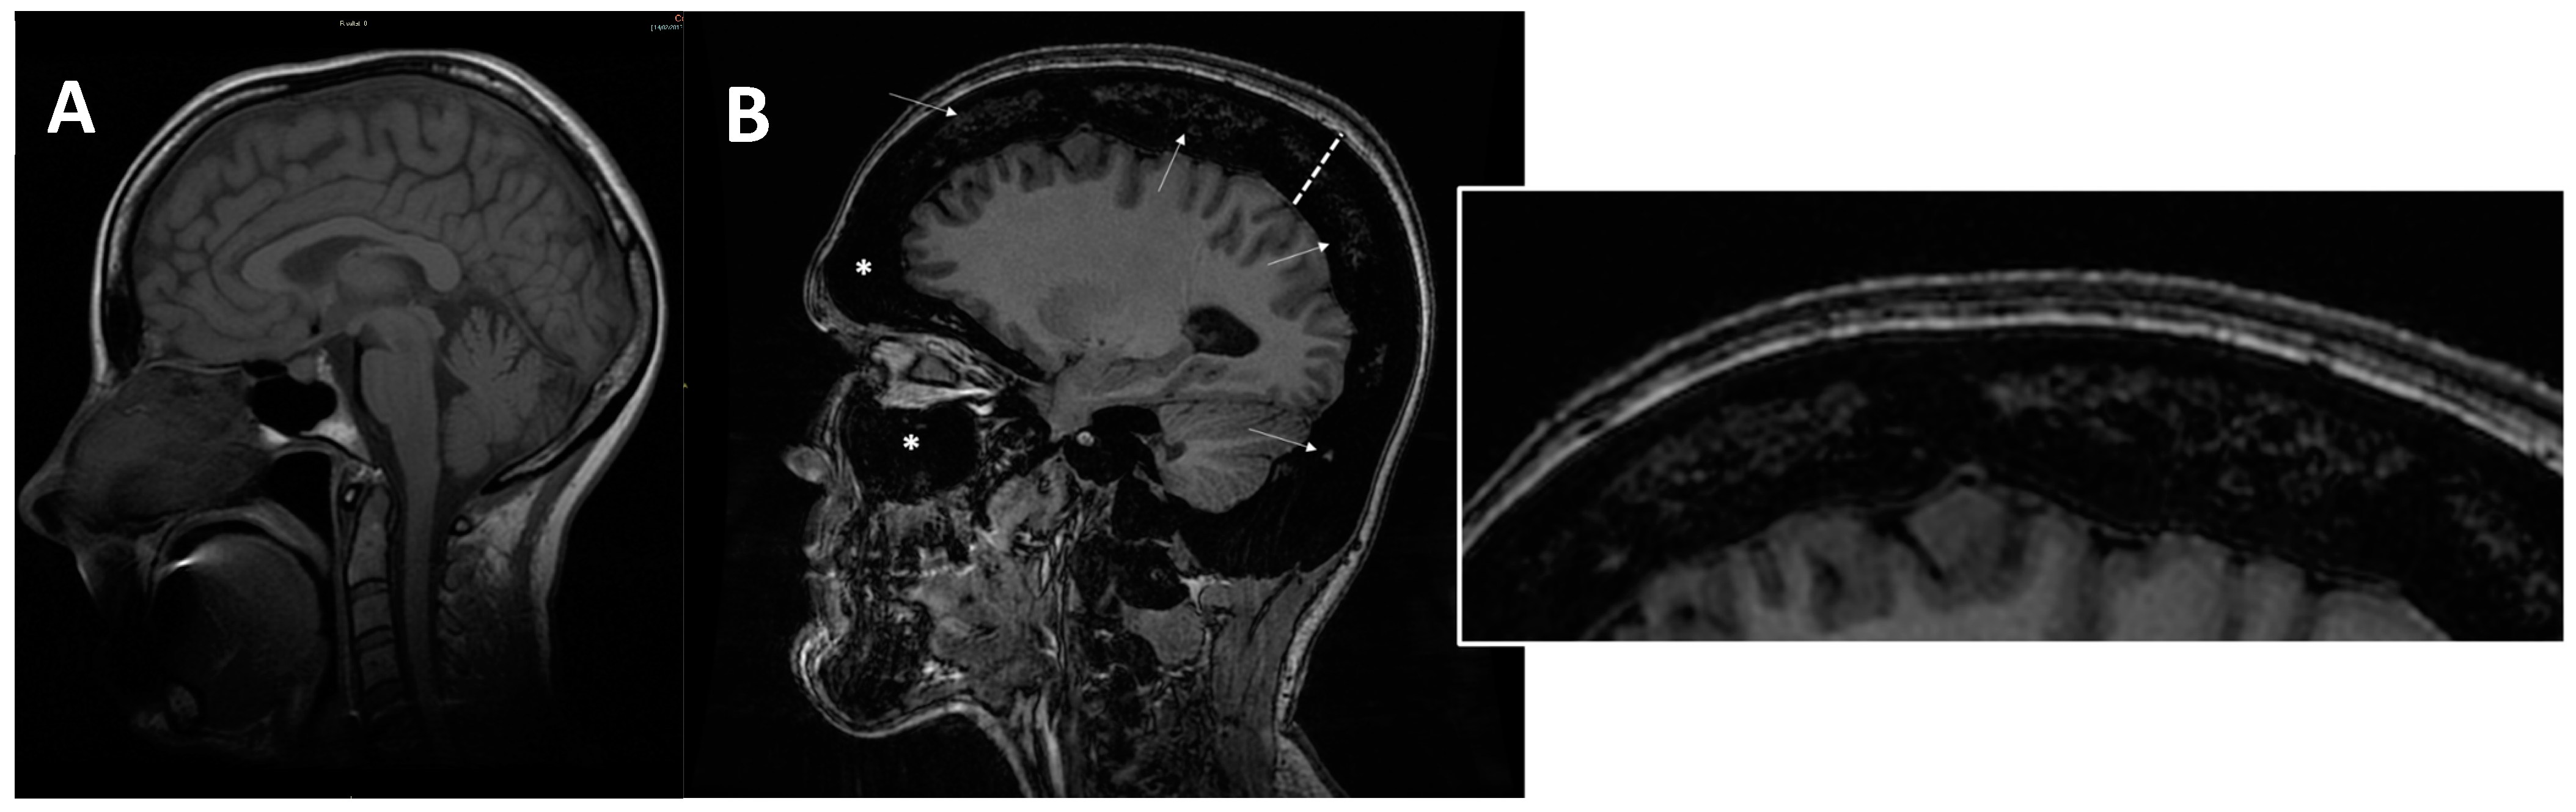

Another common group of complications is neurological involvement, which can be found in patients with ARO or IAO osteopetrosis. Imaging tools, MRIs above all, play a key role in the detection, evaluation, and follow up of neural structures damage. MRI is fundamental to assess cranial foramina (Figure 6) and brain abnormalities.

Some patients affected by ARO-type osteopetrosis may also suffer from the consequences of reduced bone marrow space (Figure 7), resulting in deficiency of all types of blood cells (pancytopenia), extramedullary haematopoiesis (e.g., in spleen, liver), and can experience the development of myeloid tissue in extramedullary sites (myeloid metaplasia).

As detailed in the cases described, increased bone density was found in all OP types with different degrees of severity assuming a ‘Marble Bone Appearance’, especially in the ARO type, whereby the ‘Erlenmeyer flask deformity’ of the metaphysis of long bones was found particularly on femurs (more frequently in ADO type 2, but also in ARO and IAO), a ‘bone in bone’ appearance was more frequent in ADO type 2 and less frequent in ARO and IAO, and a ‘rugger-jersey spine’ appearance was found in ADO type 2. The thickening and sclerosis of the calvaria or skull base abnormalities are usually found in all osteopetrosis types, even if with different radiological patterns [27]. Indeed, in the ARO type, a diffuse sclerosis of the skull is usually found, together with a thickening of the skull base and calvaria. In the ARO osteopetrosis type, alterations of the facial bones can be found too; particularly hypertelorism, with a so-called ‘space alien’ appearance on the frontal radiographs described in children. Poor pneumatization or the complete obliteration of the paranasal sinuses can be detected on imaging studies of patients with ARO-type osteopetrosis (see Figure 7) [28].

Figure 6. (A) axial MRI of a healthy young female (shown as comparison). (B) axial MRI (T2w*) of a 38-year-old female with a clinical-radiological diagnosis of osteopetrosis (ARO type); narrowing of both optic foramens can be noted (arrows) caused by a diffuse bone thickening. Diffuse bone thickening of cranial bones is associated with a marked ipointense signal intensity of all the skeletal structures related to the diffuse bone sclerosis (asterisks).

Figure 7. (A) axial MRI of a healthy young female (shown as comparison). (B) sagittal MRI (proton density sequence) in ARO-type osteopetrosis patient suffering from anaemia (Hb = 7g/dL) shows markedly reduced bone marrow space (arrows and enlargement on the right); diffuse calvarias bone thickening (dotted line), sclerosis (signal hypointensity), and obliteration of maxillary and frontal paranasal sinus (asterisks) can be noted.